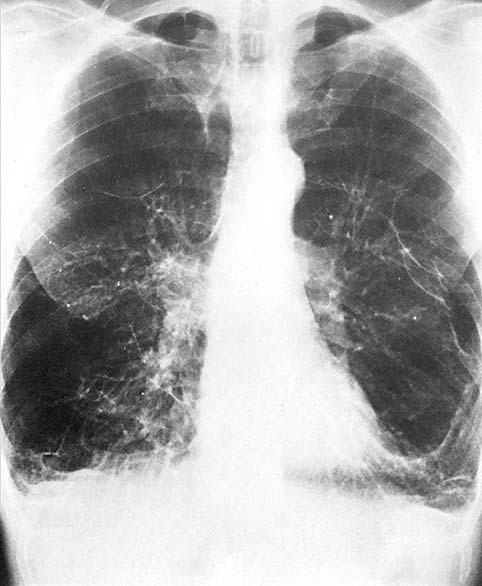

Stafylokokkenpneumonieën verlopen ernstig en geven vaak aanleiding tot complicaties. Ze zijn gevreesd als complicatie bij influenza, komen voor bij intraveneuze druggebruikers en zijn bekend als ziekenhuisinfectie (afb. 7.6b).

De pneumonie kan zich acuut maar ook geleidelijk ontwikkelen. Zij is vaak dubbelzijdig en maakt de patiënten erg ziek. Hoge koorts en cyanose zijn aanwezig. Het etterige sputum kan bloed bevatten. Abcedering van het infiltraat, pleuritis exsudativa en empyeemvorming komen nogal eens voor als complicatie. Tevens kan zich een shock ontwikkelen.

De behandeling bestaat uit het toedienen van een gericht antibioticum omdat stafylokokken steeds vaker penicillinase maken en zo resistent zijn geworden tegen penicilline. Indien aanwezig moeten de shock en hypoxie adequaat bestreden worden.